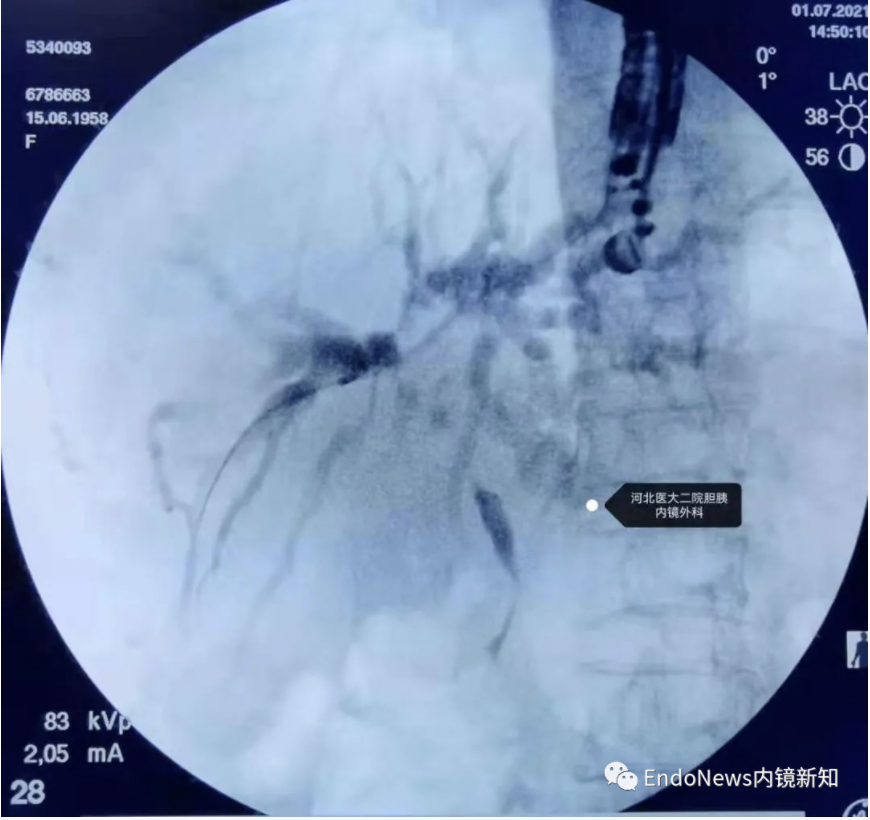

行经十二指肠胆管穿刺(CDS)时一般不需要考虑以上问题,但如因某些特殊原因涉及到会师操作时可能涉及到导丝自胆总管上游朝向下游的超选。一般情况下,CDS的时候穿刺针的方向是朝向肝内的,比如下图:

如果这个时候放支架行CDS就可以结束手术了,如果需要做顺行或者会师,就需要使导丝返折180°朝向胆管下游方向穿出十二指肠乳头。